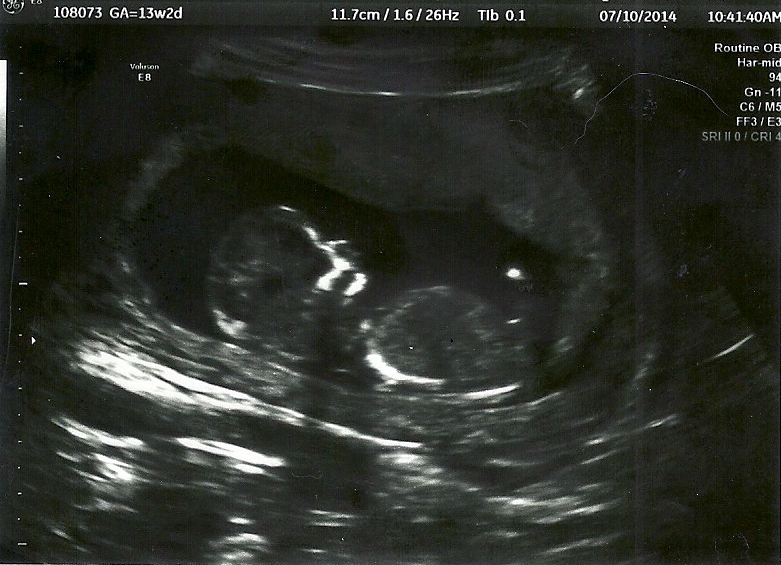

Any guesses? I was 13w2d

Scanned pic 13w2d. may not be any better but the camera on the 1st one made it look way lighter.